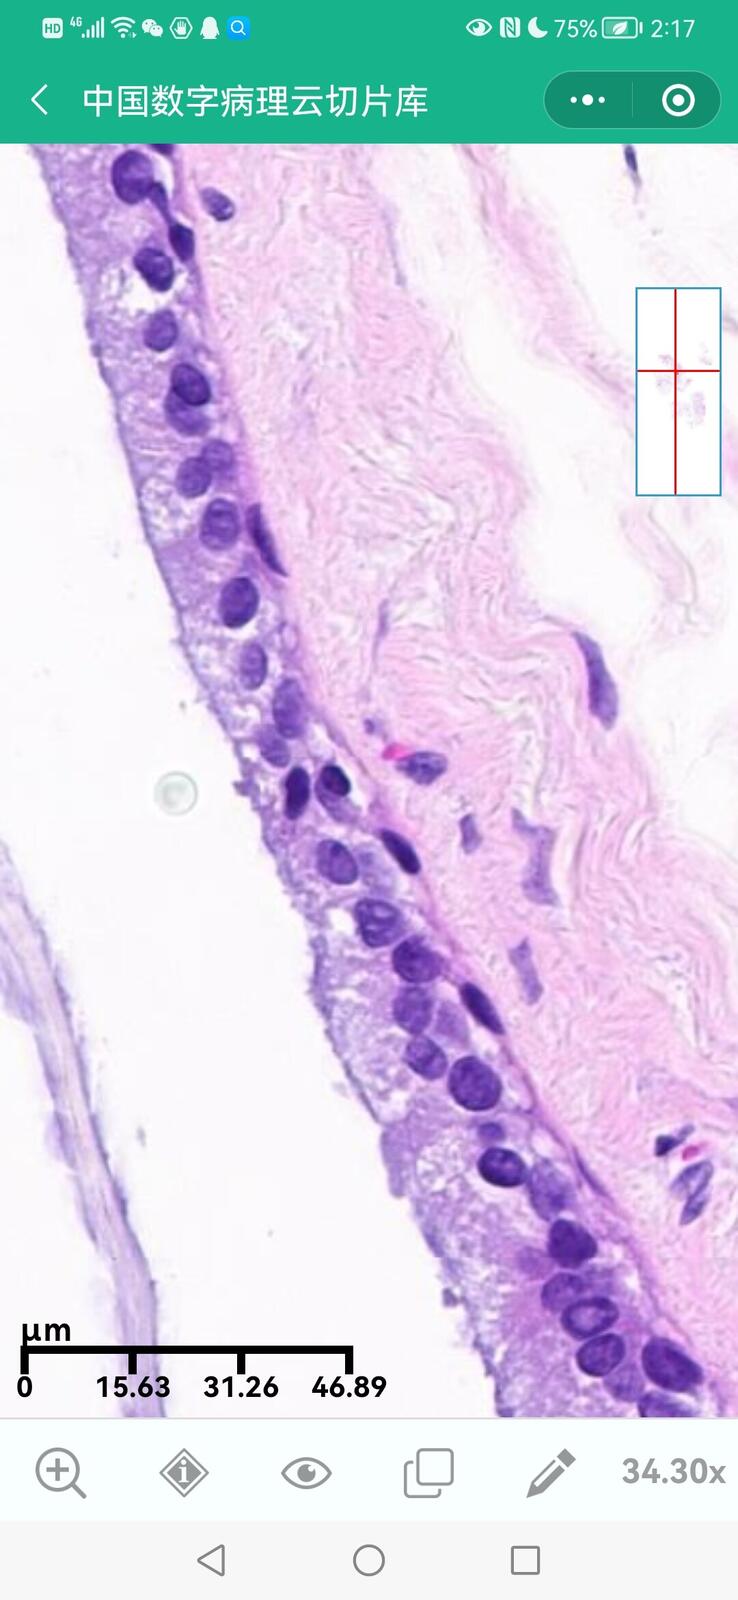

乳腺黏液性囊腺瘤伴导管内癌